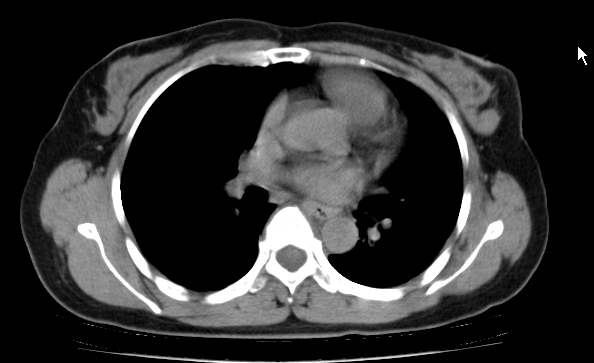

标题: CT25227:背部疼痛伴双侧胸壁痛2月,食欲差。 [打印本页]

标题: CT25227:背部疼痛伴双侧胸壁痛2月,食欲差。

肺结核并胸椎结核?请各位高手指教。

用椎体的条件来扫胸椎呀!考虑1左侧胸膜小结节形成2椎体结核并冷脓肿形成

考虑胸椎结核并椎旁软组织肿胀。

左肺结核灶,胸椎结核并冷脓肿。

左肺结核灶,胸椎结核并冷脓肿